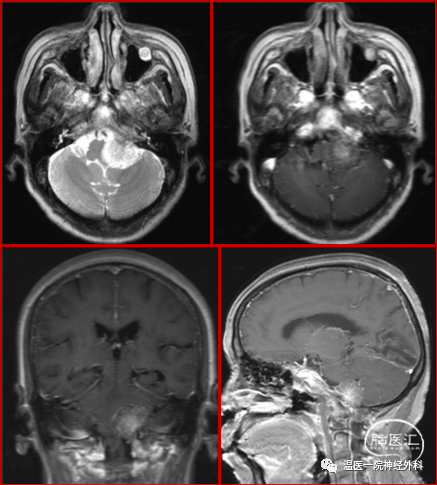

影像资料:

图1 术前MRI平扫+增强

患者入院后完善相关检查,根据症状、体征及影像学资料,入院初步诊断考虑左侧枕大孔区及右侧额叶脑膜瘤,手术指征明确,此次拟先行左侧远外侧入路开颅肿瘤切除术。

进一步分析枕大孔区病变影像学特点,考虑病变位于脑干腹外侧,椎动脉V3段上方,且病变本身通过对周围组织结构挤压已形成向后方的“天然走廊”,预估术中无需追求对枕髁的磨除,亦不必向下方过分暴露,所以拟采用开颅损伤及操作风险相对较小的改良远外侧手术入路。